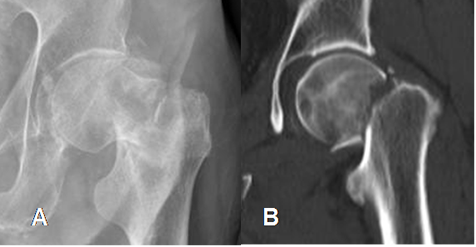

Fig 45. Fractura oculta.

TAC reconstrucción coronal. Fractura transcervical oblicua y lineal, no vista en la Rx simple. ( No mostrada).